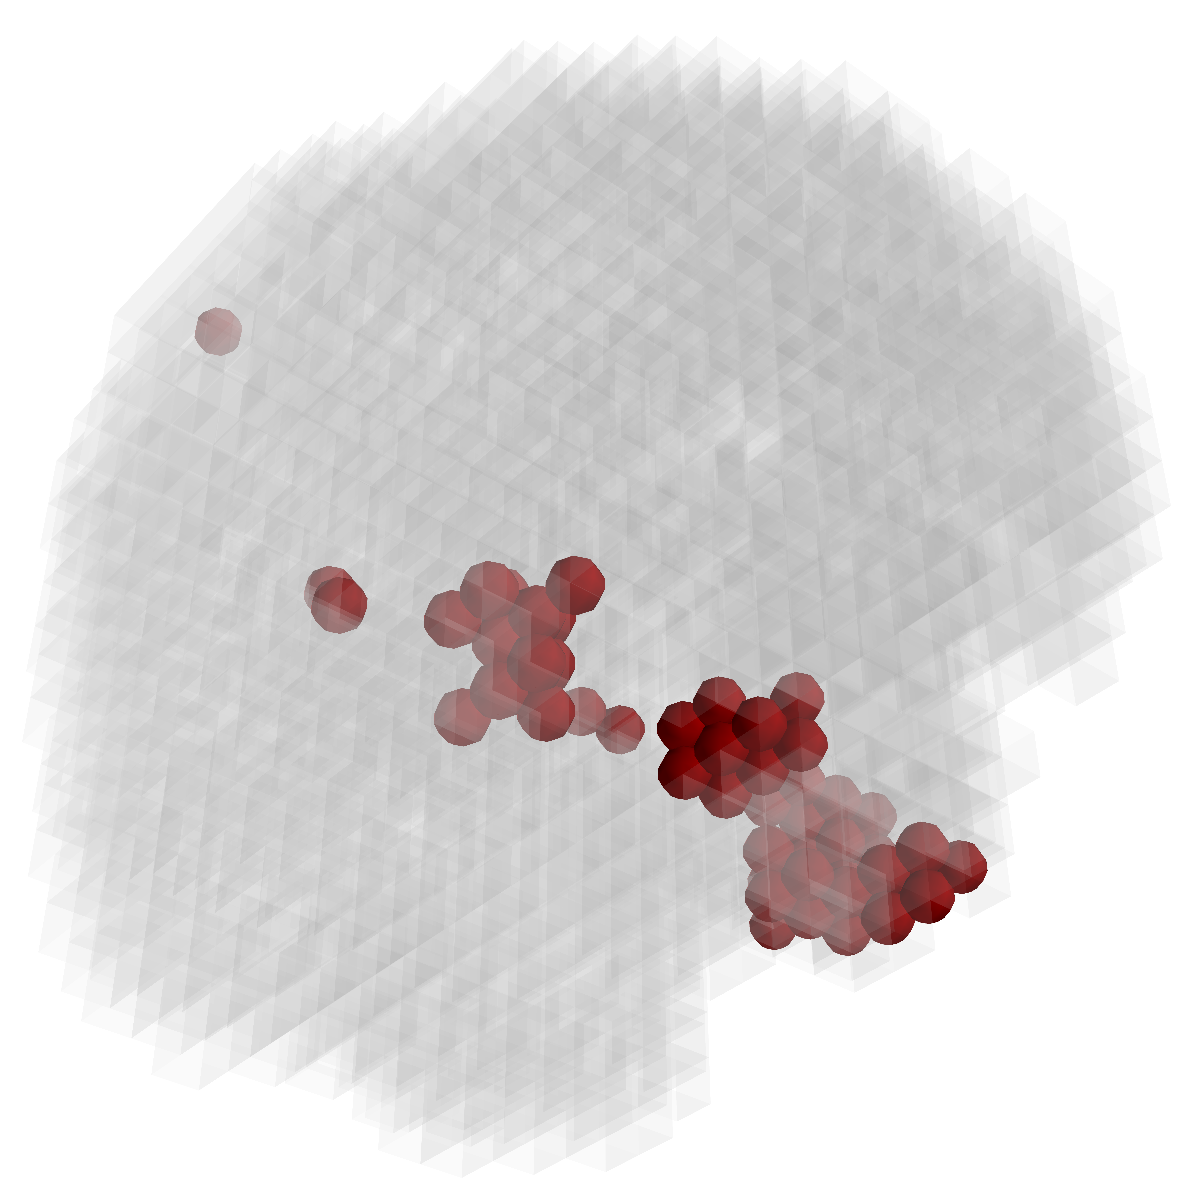

Figure 3: Stability of selected voxels across different folds of the cross-validation. The results of 5 different folds are shown in (a)-(e). The voxels with positive β𝛽\beta are in brown, negative ones are in blue. The common/overlapped voxels selected in all 10 folds are shown in green (f). The top row illustrates voxels selected by the lasso model, the mid row illustrates those of GFL and the bottom row shows those of n2superscript𝑛2n^{2}GFL.

Feature Stability. In Figure 3, we show the selected voxels across different folds of CV333Here, parameters were determined by accuracy. Similar results were observed using parameters producing same level of sparsity.. As shown, the selected voxels by lasso vary much across different folds, whereas the selected voxels by GFL are more stable. However, by assuming the positive correlation between the features and the disease labels in n2superscript𝑛2n^{2}GFL, we further increase the stability. To quantitatively evaluate the stability gain, we denote the variables of the k𝑘kth fold of CV as 𝜷(k)𝜷𝑘\boldsymbol{\beta}(k). We introduce two measurements here. In (?), the Estimation Stability (ES) is proposed to measure the stability of the estimation

where ##\# is the number of elements in a set. In Tab. 3, both measurements quantitatively suggest n2superscript𝑛2n^{2}GFL obtains much more stable voxels due to the consideration of the correlation between the features and the disease labels 444We notice that, in (?), the stability is computed using the top 50 positive voxels because these voxels are believe to be the most atrophied ones. By computing the stability of all non-zero voxels, the mDC of GFL drops around 30%percent3030\%. This clearly shows that the instability is caused largely by the undesirable voxels that disagree with the correlation prior (those scattered blue voxels in the mid row)..